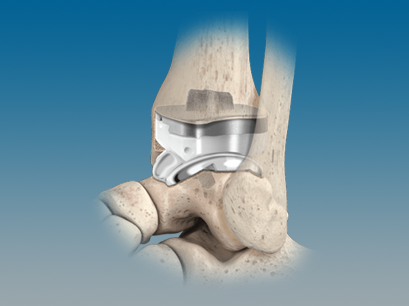

QUANTUM® Total Ankle System with OrthoPlanify™ Patient Specific Instrumentation